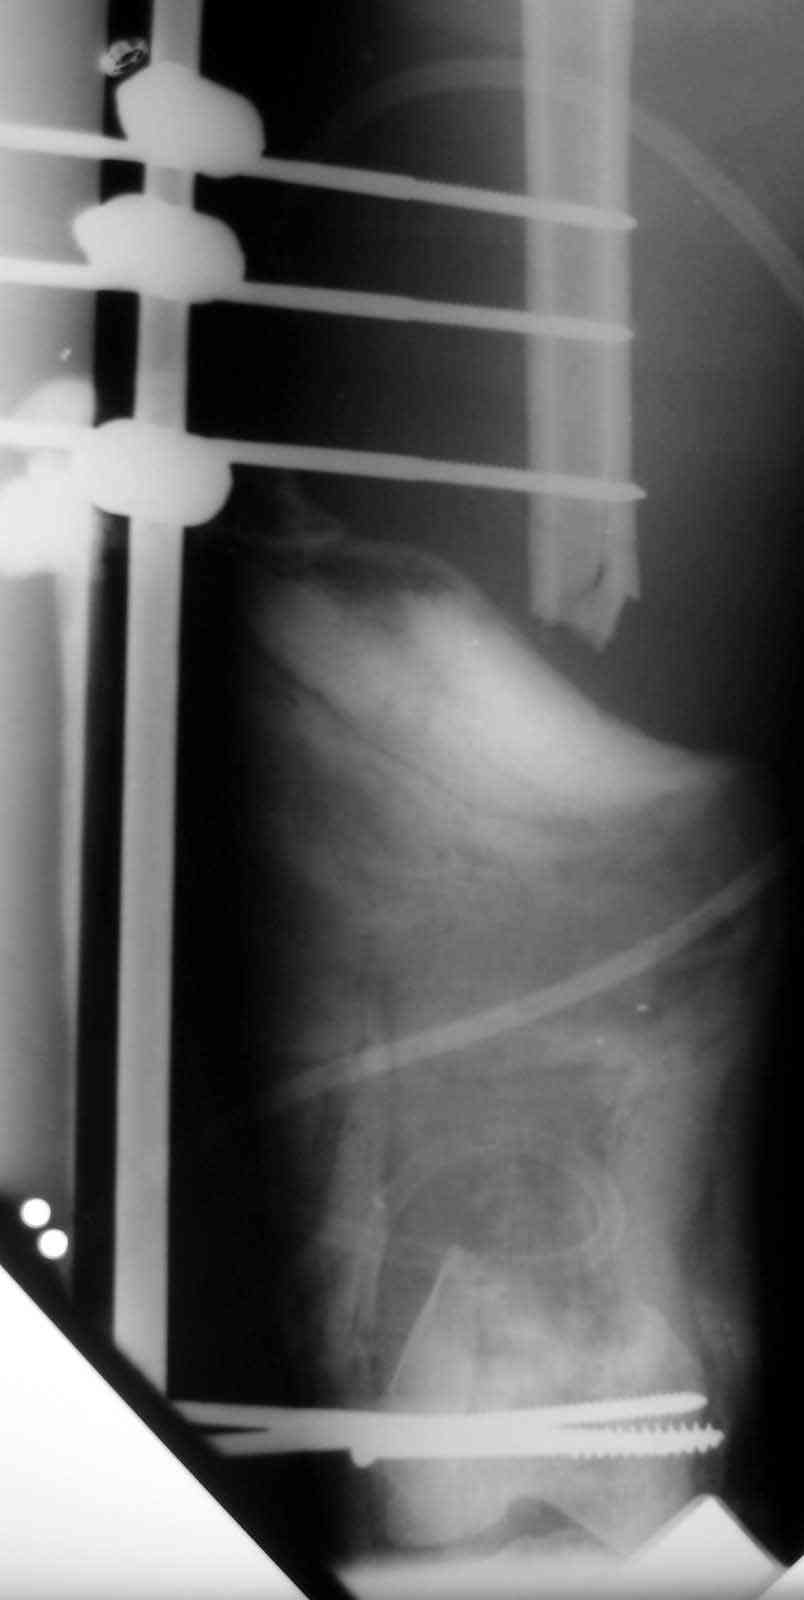

I have done both for this problem and I feel Ilizarov bone trnapsort is the

best[ probably only ]answer. Vasc fib graft in the femur especially in this

regeon has a problem ie; inadequate fixation distal fragment and long period

to hypertrophy.

With Ilizarov you need a mid shaft corticotomy and trnasport. The frame

needs to extended down to the tibia with hinges across the knee